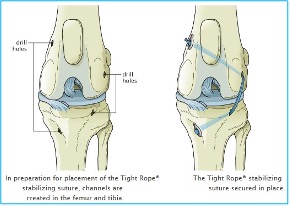

Q: What Is the Tightrope CCL Procedure for a Torn ACL?

A: The Tightrope CCL Procedure is an advanced variation of the lateral suture technique used to stabilize a torn cranial cruciate ligament (CCL) in dogs. It involves placing a strong artificial ligament outside the joint to mimic the function of the natural CCL. Learn more about TightRope techniques.

Advantages of Tightrope CCL:

Stronger than traditional lateral suture techniques. Learn about lateral suture repair technique.

Minimally invasive compared to bone-cutting procedures

Can be an option for medium to large-breed dogs

Disadvantages of Tightrope CCL:

Uses braided material, which can trap bacteria and lead to infection if contamination occurs.

Still relies on scar tissue formation for long-term stability.

Not as biomechanically sound as TPLO surgery, especially for active or large dogs.

While Tightrope CCL is an improvement over standard lateral suture techniques, TPLO surgery remains the gold standard for long-term stability, function, and arthritis prevention, especially in large, active dogs.